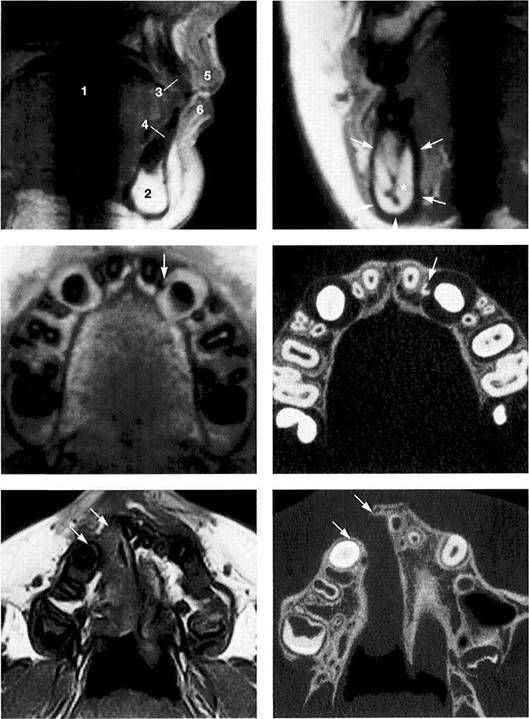

Computed Tomography of the Temporomandibular Joint and its Anatomical Correlation

Lateral portion of the joint

A computed tomogram and a macroscopic anatomical prepara­tion of the lateral portion of a human temporomandibular joint. Left: Because the CT machine was not fitted with a soft-tissue win­dow, the soft tissues cannot be identified. The low thickness of the slice causes some of the marrow spaces to appear as cavities (ar­rows).

Right: Because in this specimen the insertion of the lateral pterygoid muscle lies farther lateral than usual, part of the tendon (outlined arrows) can be recognized.

Central portion of the joint

Pictures of the central portion of the same joint. Notice the precision with which the CT reproduces the contours of the osseous structures (arrows).

Medial portion of the joint

In addition to the contours of the fossa and protuberance, the cancel­lous bone of the condyle is promi­nently reproduced in the medial slice of the joint as well. The ability of CT to accurately reproduce the bony articular surfaces should not mislead one into thinking that CTs are absolutely necessary for all tem­poromandibular joint problems. They are practical for joint deforma­tions associated with syndromes, fractures, ankylosis, or tumors, but all other joint surface lesions can be adequately diagnosed through other clinical procedures (see also p. 68).